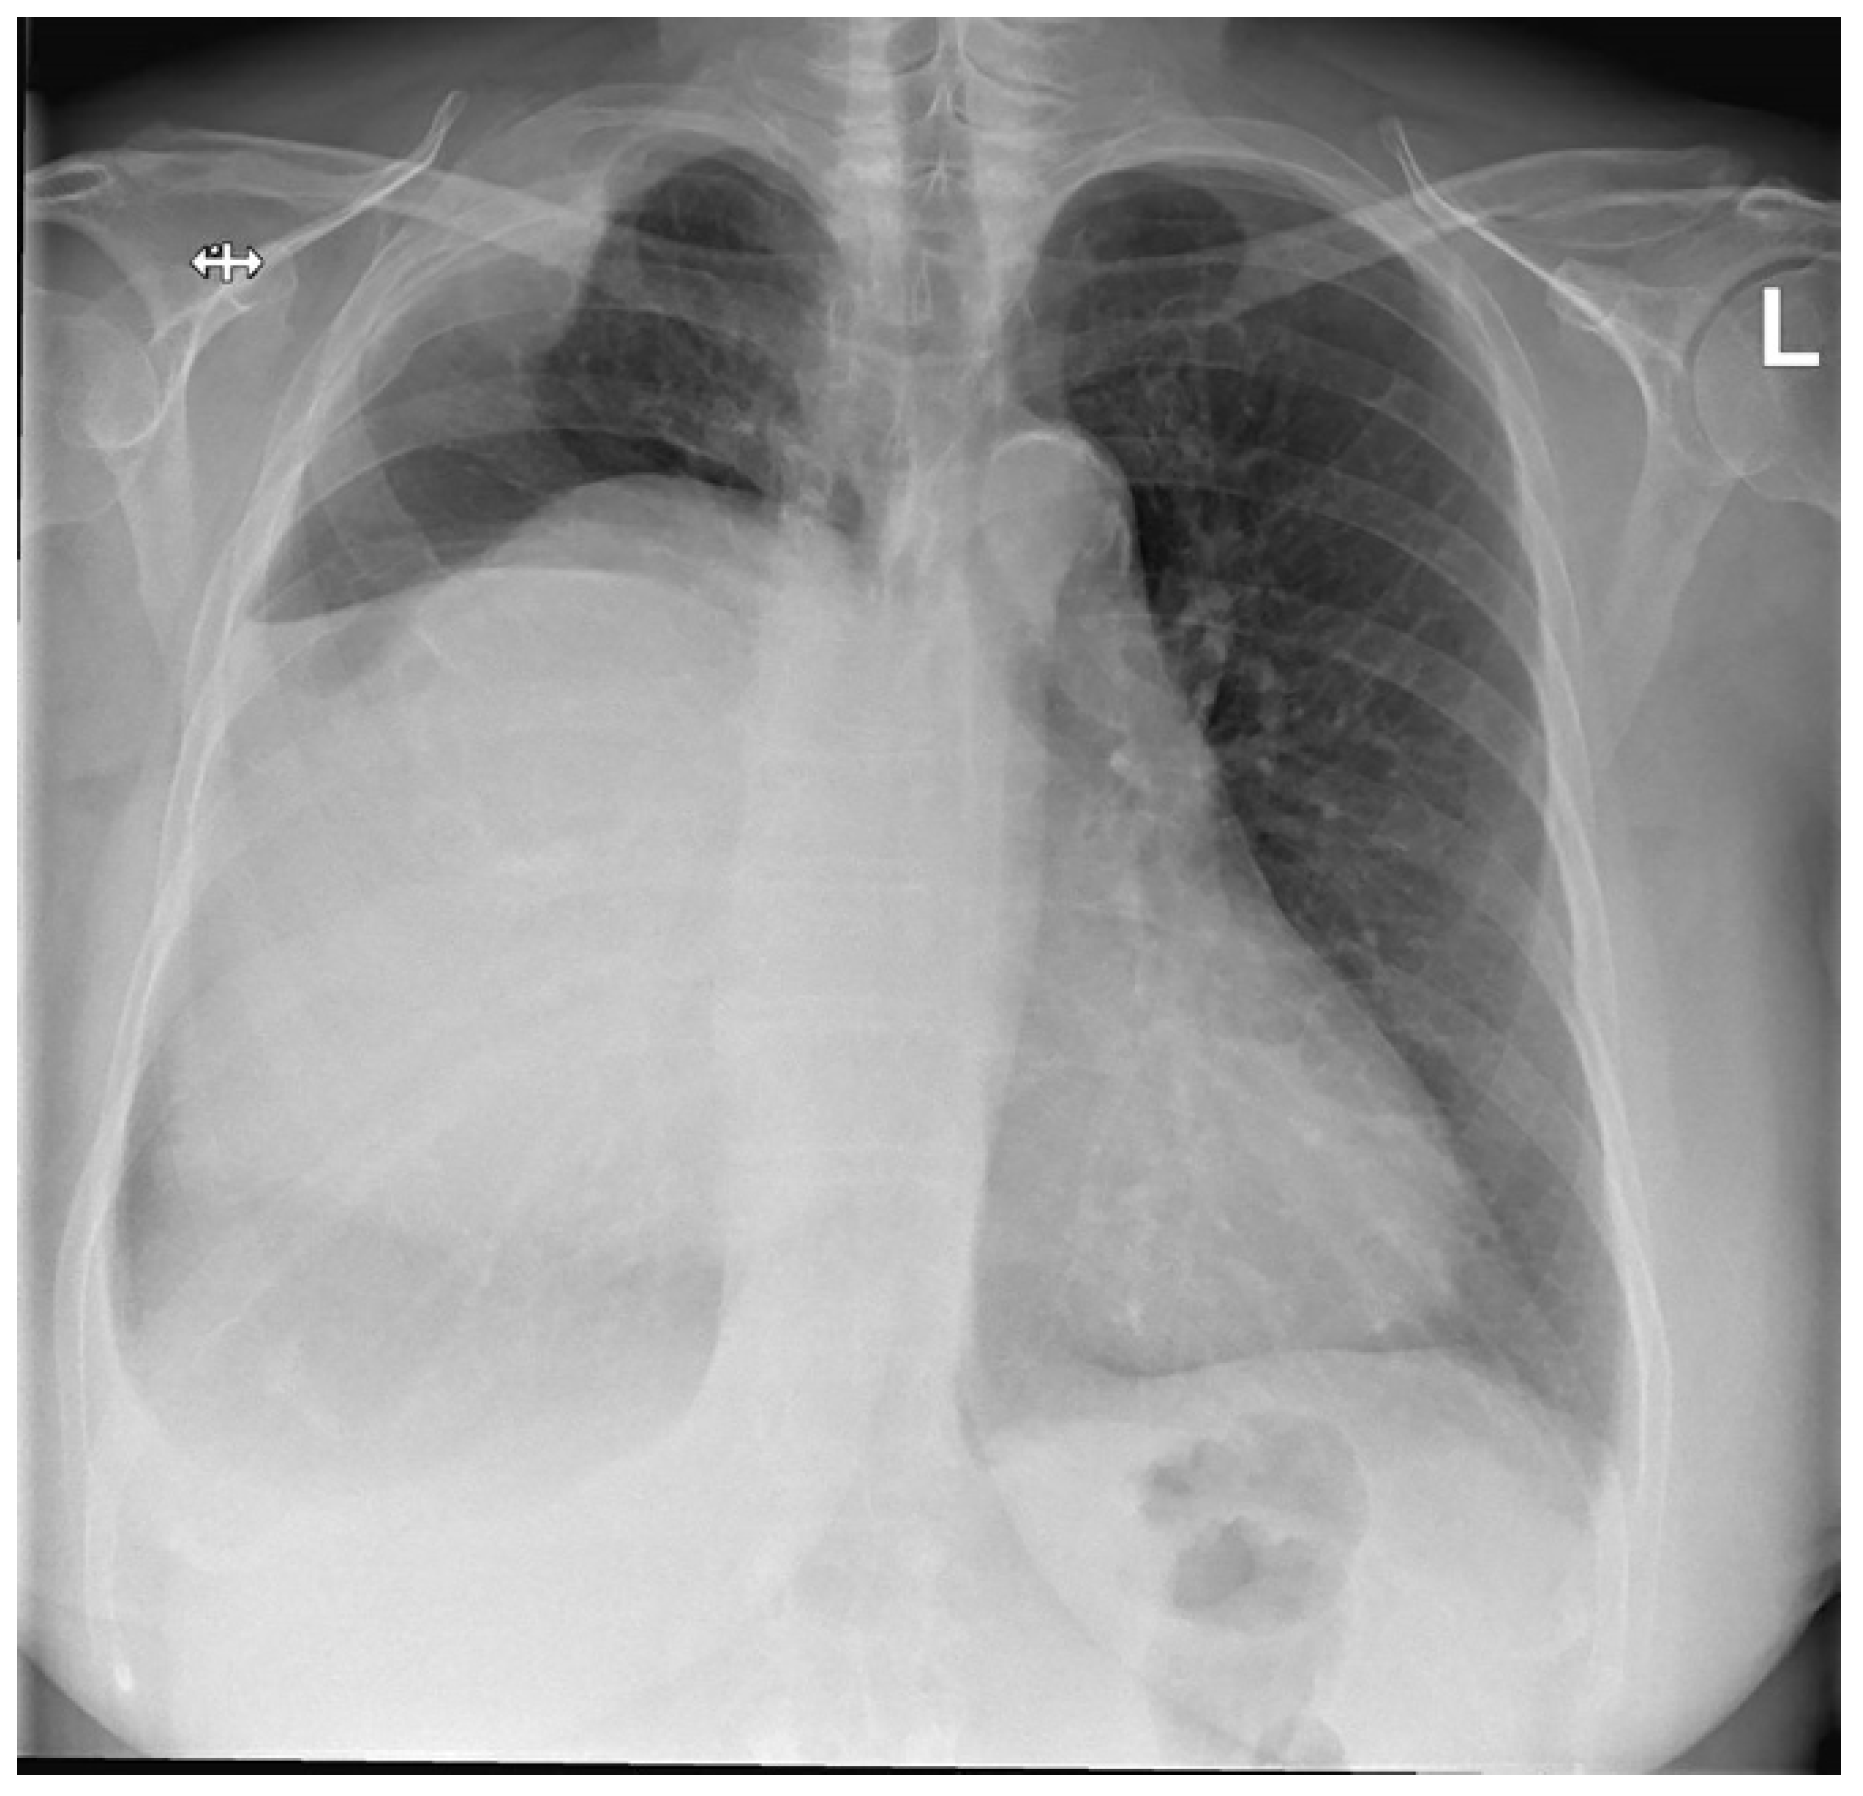

She developed complaints of progressive dyspnea and impairment of quality of life after approximately 2 years of follow-up. A chest X-ray was performed and demonstrated progressive growth of the mass together with a displacement of the mediastinum to the left (Figure 1).

Figure 1. Preoperative posterior–anterior chest X-ray. Evidently increased density of the right hemithorax. The right hemidiaphragm cannot be clearly distinguished, most likely as a result of the large soft tissue mass displacing the mediastinum to the left. In addition, morphological changes of the right lateral side of the second and third rib are visible, with intrathoracic enlargement of the soft tissue.